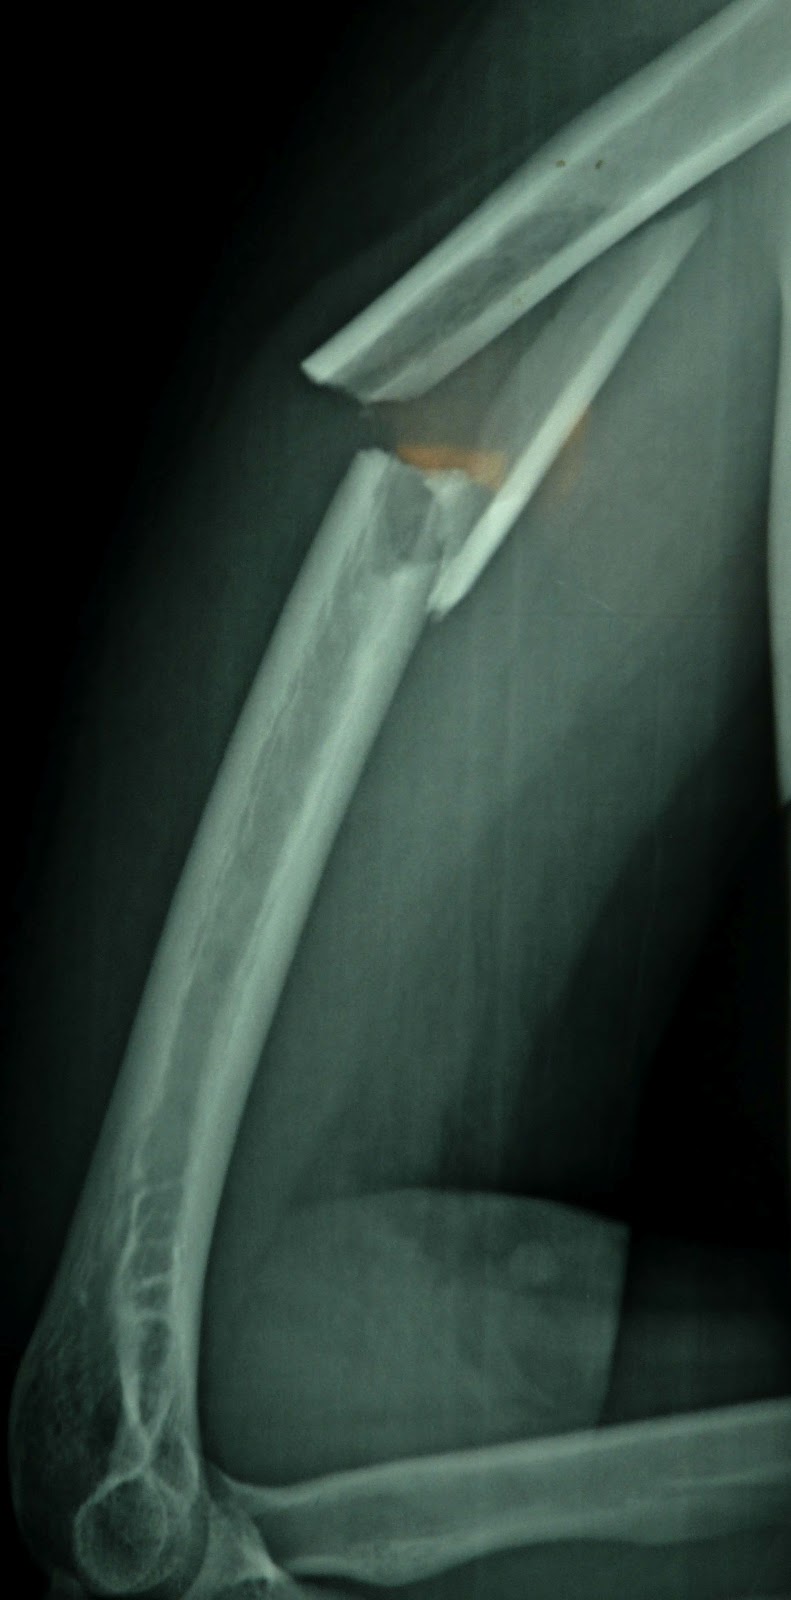

O R T O C R I T I C A Fractura expuesta humeral con lesion del nervio radial